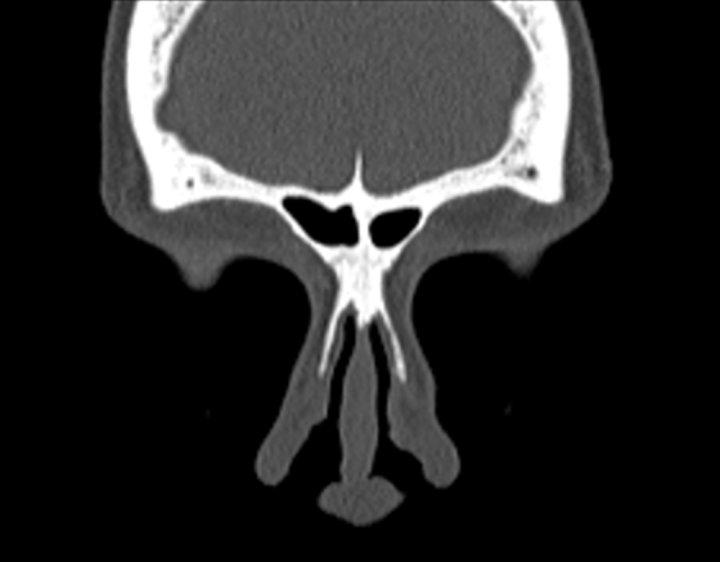

Click any image for labels.